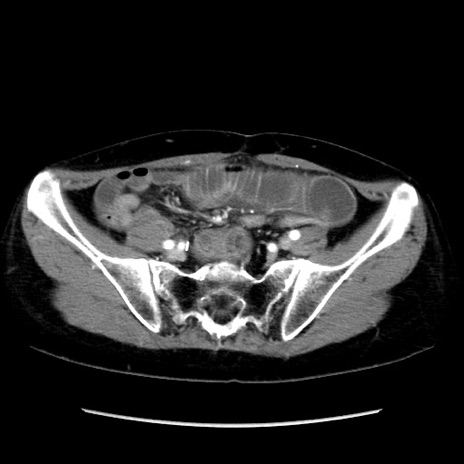

症例32(横断像)

【症例】40歳代 女性

【主訴】上腹部痛、嘔気・嘔吐

【現病歴】約9時間前頃から急に上腹部痛、嘔気、嘔吐が出現。改善しないため救急要請。

【既往歴】子宮頚癌(広汎子宮全摘術、放射線療法)、腸閉塞

【身体所見】腹部:平坦、軟、腸雑音亢進、上腹部を中心に腹部全体に圧痛あり。